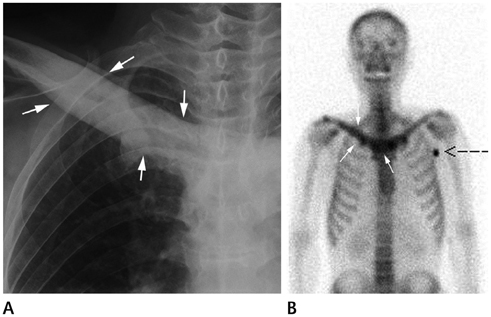

Systematic Approach of Sclerotic Bone Lesions Basis on Imaging Findings

- Sclerotic bone lesions are common, but there are diverse groups of tumors and non-tumorous lesions. Although plain radiograph and computed tomography can reveal important characteristics of these lesions, diagnosis is often challenging for radiologists. A systematic approach and familiarity with the imaging features of various sclerotic bone lesions may be greatly helpful for eliminating in the differential diagnosis. This review describes the systematic approach to diagnosing sclerotic bone lesions based on imaging findings.